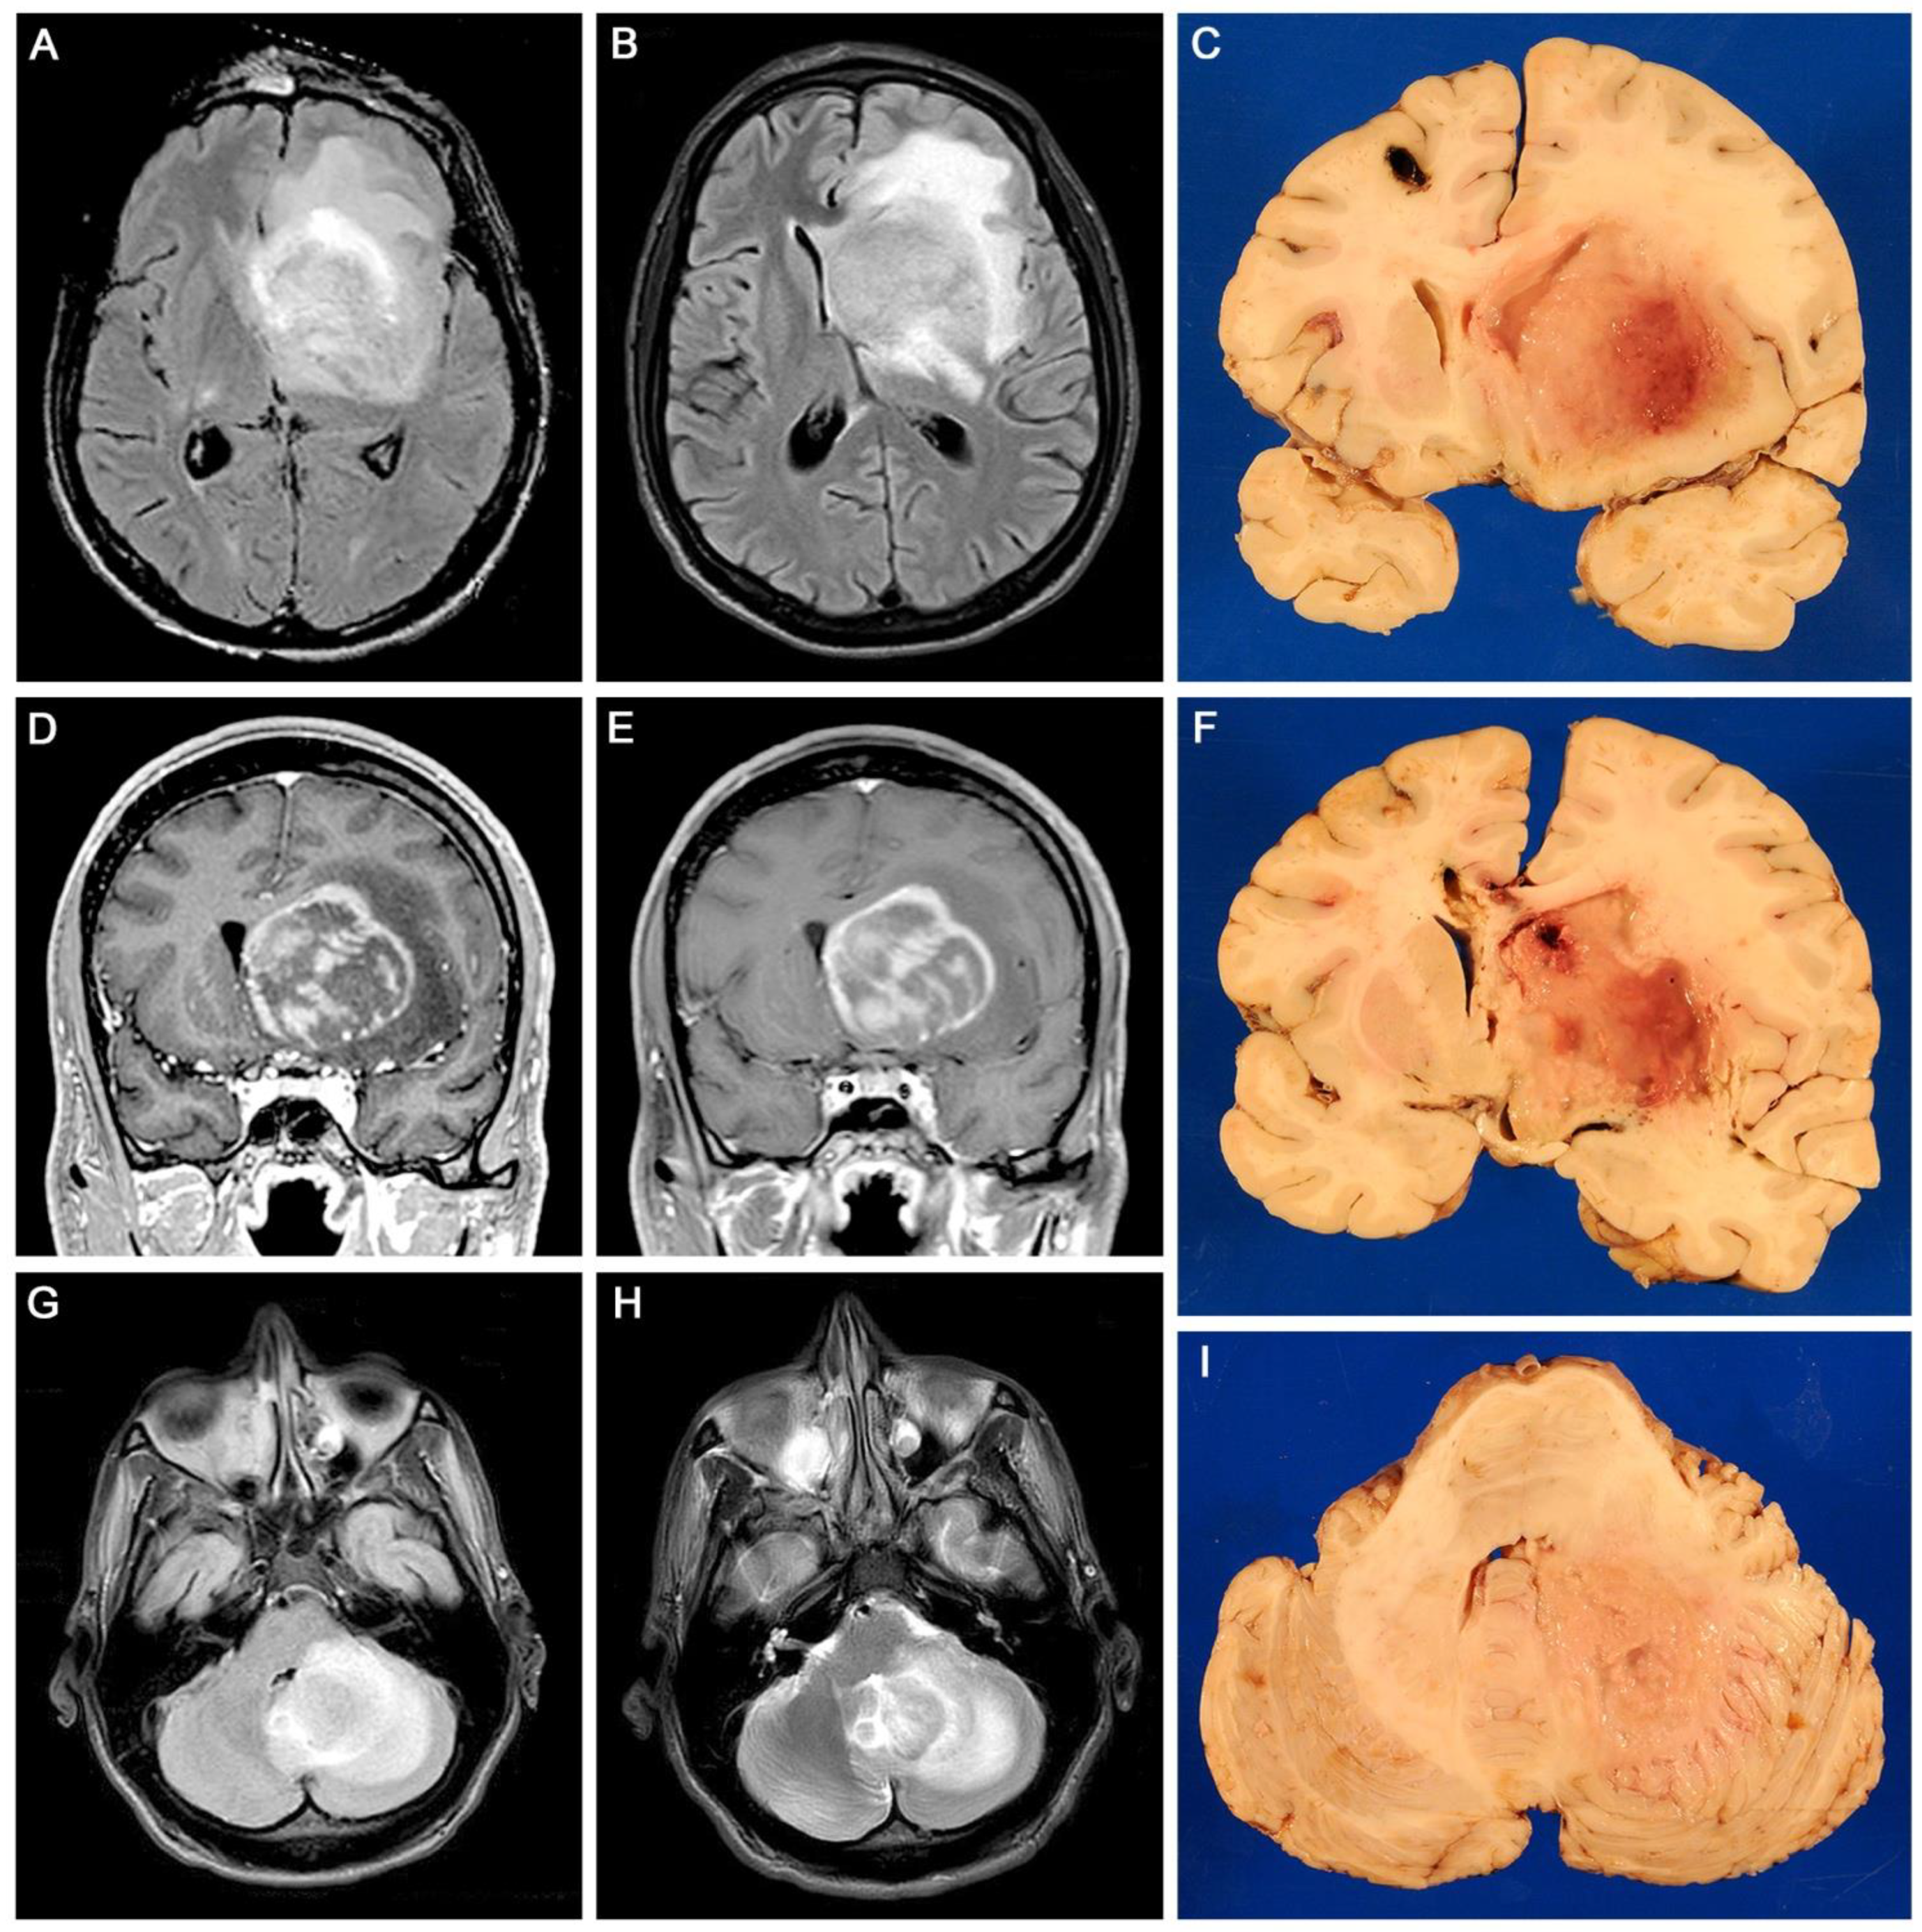

3.1. Gross and Histopathological Aspects of the Tumor